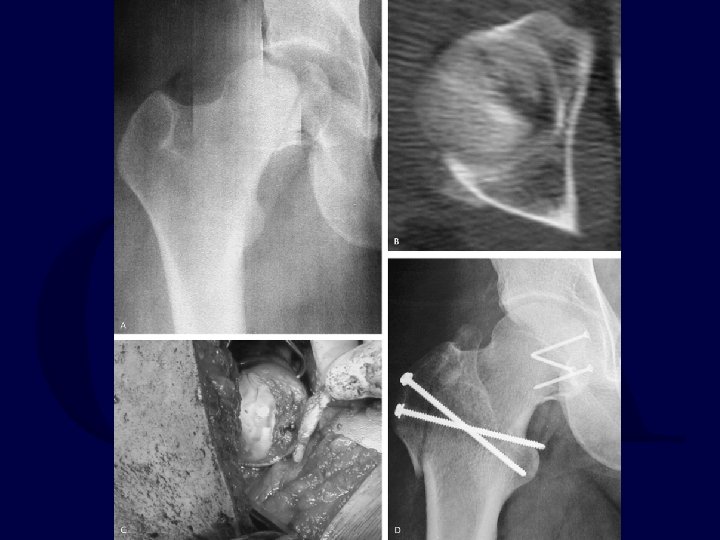

2. Hip Dislocation with Femoral Neck Fracture Usually the dislocation is posterior. Thus, Kocher-Langenbeck approach. If fracture is non-displaced, stabilize fracture with parallel lag screws first. If fracture is displaced, open reduction of femoral head into acetabulum, reduction of femoral neck fracture, and stabilization of femoral neck fracture.

Pipkin III Fractures High incidence of AVN and degeneration with displaced fractures. – Relative indication for hemiarthroplasty in older patient due to this risk – Attempt at ORIF warranted in active, younger patients If femoral neck fracture is non-displaced, do not attempt manipulative reduction of hip until femoral neck is stabilized.

Femoral Head Fracture-Dislocation with Displaced Femoral Neck Fracture • Closed reduction attempts are futile. • ORIF in young: open reduction of hip, then reduction and stabilization of femoral neck and head. • Arthroplasty in middle-aged and elderly (No good results with ORIF reported in literature).

Femoral Head Fracture-Dislocation with Non-Displaced Femoral Neck Fracture Must consider stabilizing femoral neck fracture before performing reduction of hip.